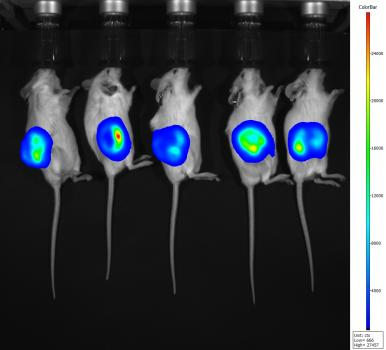

5.荧光标记物示踪(Ex735/Em810荧光通道)

DiR染料标记293细胞,尾静脉注射后拍摄(左右二列间隔半小时拍摄;第一行均为对照组,第二行均为实验组)

实验组解剖后拍摄(肝脏、肺、脾脏有明显信号)